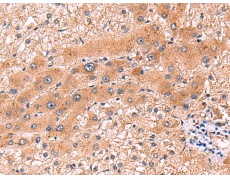

IHC positive control: |

Human liver cancer |

IHC Recommend dilution: |

80-400 |